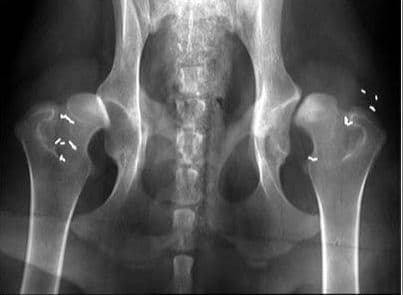

Chữa bệnh viêm khớp háng ảnh hưởng đến sinh hoạt và cuộc sống

Bệnh viêm khớp háng kéo theo những cơn đau nhức dữ dội, khiến người bệnh không để vận động và đi lại một cách bình thường, ảnh hưởng đến sinh hoạt và cuộc sống. Chữa bệnh viêm khớp háng như thế nào luôn là quan tâm hàng đầu của người bệnh. Bệnh viêm khớp háng […]